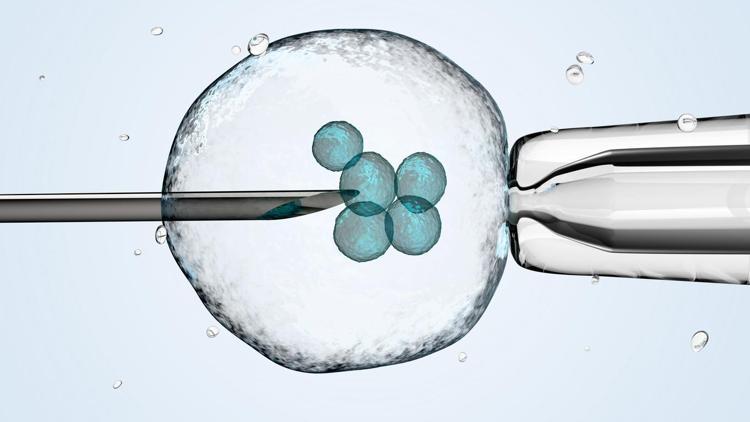

Preimplantasyon (Genetik Tarama):�Bu işlem ile embriyolar uterusa yerleştirilmeden önce kromozomal açıdan değerlendirilerek genetik taramadan geçirilir. Sağlıklı bulunan embriyolar tespit edilerek transfer işlemi gerçekleştirilir.